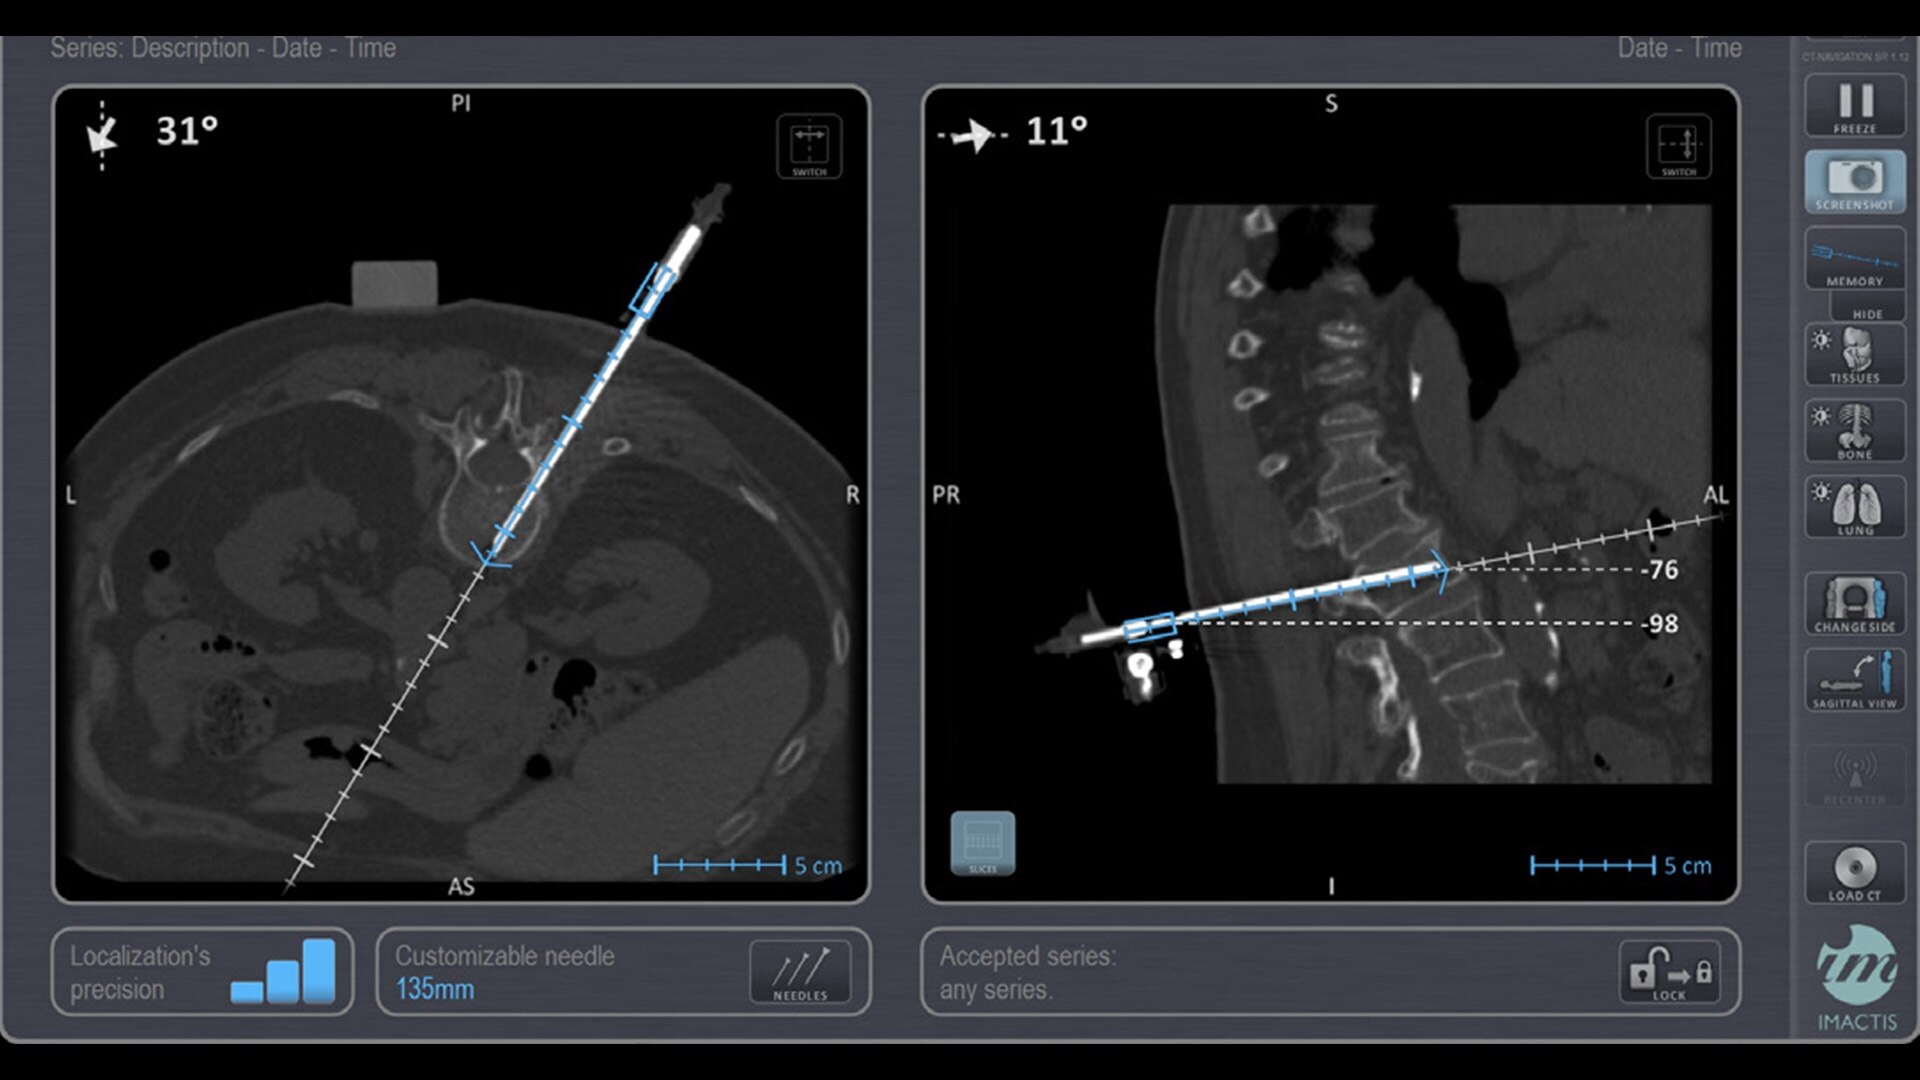

In interventional radiology, the success of the percutaneous procedure depends on correct needle positioning. The Imactis system helps the radiologist place one or more needles with great accuracy, in less time and with fewer control scans.

Imactis enables you to find the ideal path to the target.

With real-time image reconstruction, live interactive navigation and no limit in angulation, the optimal clinical choices are clear.

Live 3D needle tracking, precise reproduction of your planned trajectory and continuous needle depth measurement help ensure optimal needle placement.